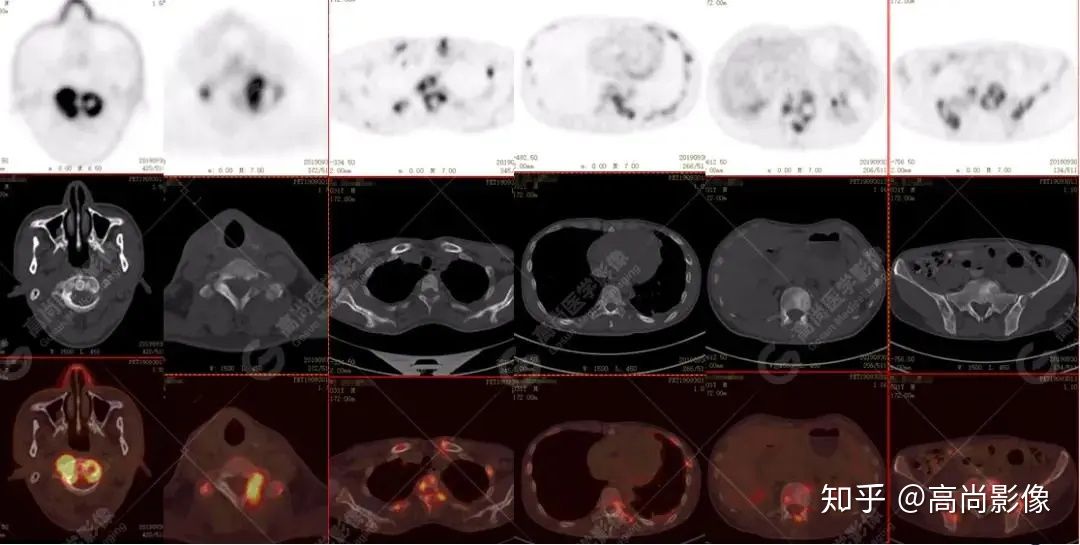

全身多發(fā)高代謝腫大淋巴結(jié),中央代謝缺損

左肺上葉尖后段及下葉背段多發(fā)簇狀斑點(diǎn)狀高代謝灶

左側(cè)胸膜結(jié)節(jié)樣增厚,代謝不同程度增高

【PET/CT提示】雙肺、左側(cè)胸膜多發(fā)結(jié)節(jié)影,全身多處骨質(zhì)破壞,全身多發(fā)淋巴結(jié)腫大,代謝攝取不均勻性增高。

特征:肺部病灶簇狀分布,上葉尖段及下葉背段為著;腫大淋巴結(jié)分布不對(duì)稱,無(wú)融合、中央有壞死改變,與淋巴瘤、轉(zhuǎn)移瘤等有一定的鑒別診斷意義;